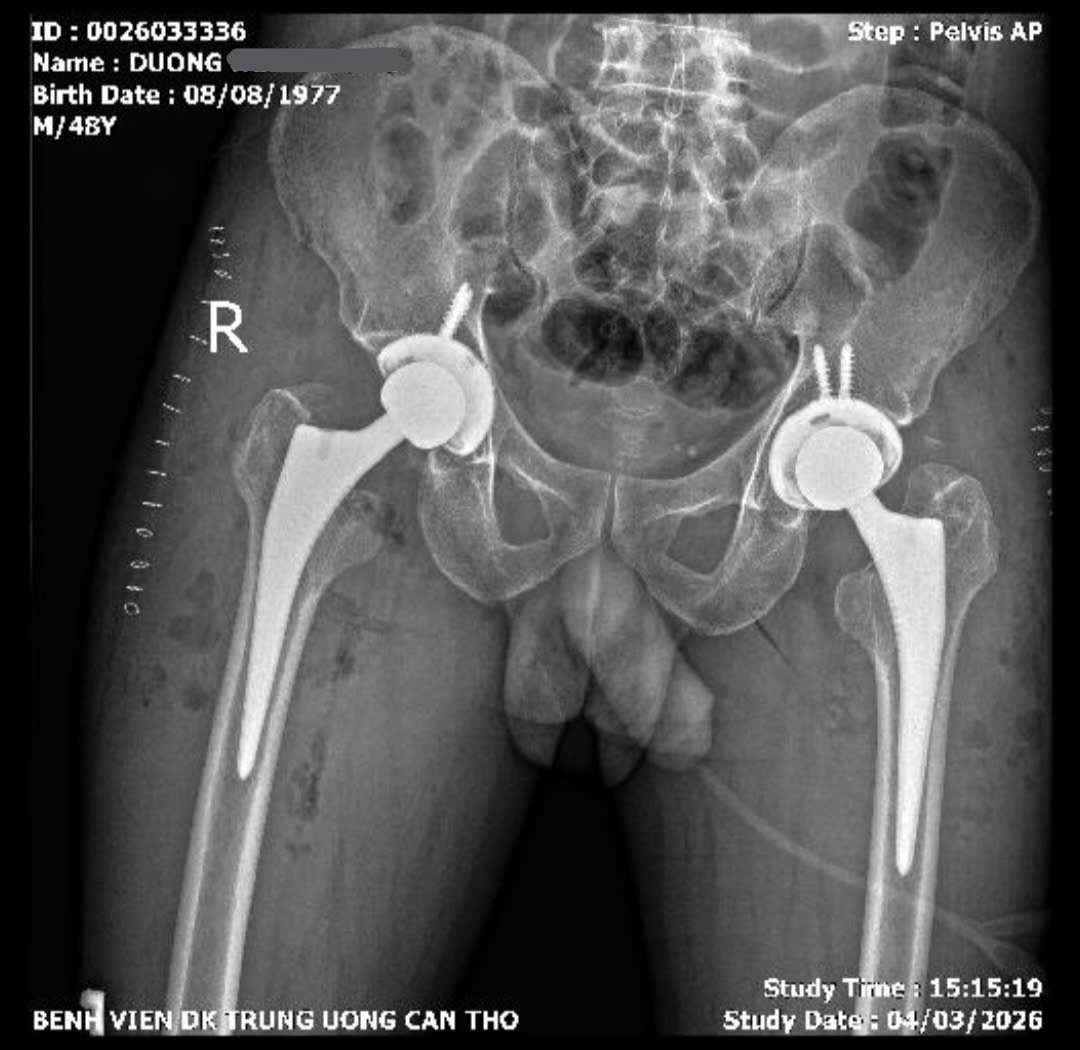

X-Quang khung chậu kiểm tra sau phẫu thuật

Thay khớp háng hai bên trong cùng một lần phẫu thuật

Ca phẫu thuật được thực hiện bởi BS.CKII. Dương Khải – Trưởng khoa Phẫu thuật thay khớp và Ung bướu học chỉnh hình, cùng ekip các bác sĩ Trung tâm Chấn thương chỉnh hình của Bệnh viện Đa khoa Trung ương Cần Thơ.

Các bác sĩ đã lựa chọn đường mổ trực tiếp phía trước – phương pháp phẫu thuật ít xâm lấn trong thay khớp háng. Ca mổ kéo dài khoảng 04 giờ, tiến hành thay khớp háng hai bên trong cùng một lần phẫu thuật.

Sau phẫu thuật, bệnh nhân phục hồi thuận lợi và đến ngày thứ 02 đã có thể tập đi lại với khung hỗ trợ và tự đi không cần dụng cụ hỗ trợ sau 05 ngày,dự kiến ra viện ngày 11/3/2026